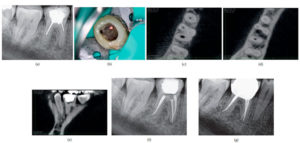

158 – Uso intraoperatorio de la CBCT para la identificación y localización de canales calcificados

Se sabe que la tomografía computarizada de haz cónico (CBCT) produce exploraciones tridimensionales de la dentición, las estructuras duras maxilofaciales y la relación de las